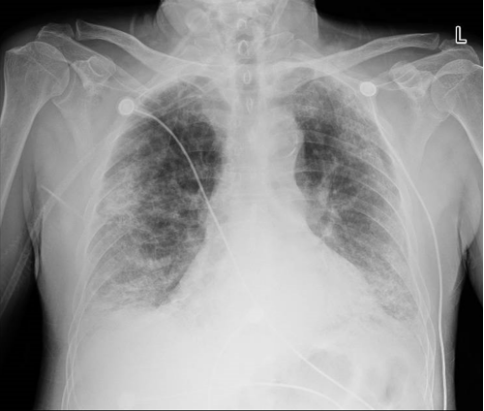

图6 ANCA相关性血管炎和MDA5相关性间质性肺病胸部CT表现病史和临床表现是临床医生特别是内科医生重要的诊断思维基础。重症ILD通常急性或亚急性起病,急性起病的ILD包括COP、AIP、AEP、HP;亚急性起病包括COP、药物相关性ILD、CTD-ILD、HP。急性、亚急性(可有发热)易误诊为肺炎。但也有一些重要线索可以帮助我们进行鉴别:季节性、聚集性发病多为感染;有免疫缺陷病史的患者多发生机会性感染;具有结缔组织病特征的患者要注意CTD-ILD;有肿瘤治疗史的患者注意考虑药物相关性ILD。当然,ILD也可以合并感染。病例:男性,28岁,高热,呼吸困难1周;1年前诊断肾病综合征,一直服用激素。T 39℃,安静状态,高流量氧疗(流速40 L/min,氧浓度70%),SaO2 93%。影像学表现为弥漫性磨玻璃影(图7)。首先考虑机会性感染—PCP。肿瘤治疗史是识别ILD的重要线索,许多肿瘤治疗新药可能会损伤肺部靶器官,例如免疫检查点抑制剂导致的间质性肺炎——免疫检查点抑制剂相关性肺炎(CIP),尽管其发生率不高,但由于此类治疗的基数较大,在临床上还是能经常见到CIP患者。所以需要了解患者免疫检查点抑制剂用药史以及影像学特征【新出现的肺部阴影(如磨玻璃影、斑片实变影、小叶间隔增厚、网格影、牵拉性支气管扩张及纤维条索影等)】,同时除外肺部感染、肿瘤进展、其他肺间质性疾病、肺血管炎、肺栓塞及肺水肿等。病例:患者, 女性, 32岁, 乳腺癌术后放化疗3年半, 靶向治疗4个月, 呼吸困难进行性加重1个月。影像学表现为磨玻璃影(图8), 氧合指数100 mmHg。诊断为药物相关性间质性肺炎。通常结缔组织病的相关体征,在呼吸系统无法识别,但一些肺外体征要引起重视,例如:眼周皮疹、披肩样皮疹、前胸V形皮疹、Gottron征、Gottron征、技工手。上述体征结合影像学表现就要考虑是否为ILD。二代测序(NGS)能够对常见和罕见的病原体进行检测,对新发病原体进行鉴定,也能鉴定常规方法难以检测的病原体,还能检测混合感染,进行菌株分型和耐药分析,在区分感染和定植方面有一定帮助。需要注意的是,对于支气管肺泡灌洗液(BALF)NGS结果,如果有强有力的证据认为不是感染,或者认为其检测出的是无意义的感染,结合患者肺部影像学为弥漫性间质改变,则要考虑非感染性疾病的诊断。病例:女性,75岁,反复咳喘3年,加重伴发热3天。曾诊断为特发性间质性肺炎,口服激素治疗1年。胸部CT可见磨玻璃影(图9)。BALF肺孢子菌核酸检测阳性,BALF-NGS回报肺孢子菌。后予激素和抗真菌治疗,患者最终好转出院。实验室检查应该作为ILD患者的常规筛查,CTD-ILD、IPAF筛查特异性抗体,结节病患者筛查ACE,系统性血管炎患者筛查ANCA。病例:女性,52岁,咳嗽15天,伴发热13天,抗Jo-1抗体阳性(+),CK、LDH增高;诊断为抗JO-1抗体综合征。患者胸部CT如图10所示。另外一例患者48岁, 全身起皮疹、关节疼痛伴发热2个月。抗黑色素瘤分化相关蛋白5(MDA5)抗体阳性; 诊断为肌病性皮肌炎-急性/亚急性间质性肺炎。患者胸部CT如图11所示。呼吸介入技术的发展为临床诊断和破解病因带来了极大的帮助,包括经支气管镜肺活检术(TBLB)、经支气管镜腔内超声(EBUS)、冷冻肺活检、电磁导航技术等。对于重症ILD患者,是否借助于这些技术以及选择哪种技术,需要综合患者的病情而定,充分考虑其必要性以及安全性。病例:女性,65岁;间断咳嗽半年余,呼吸困难伴心慌2天入院;呼吸窘迫,氧合指数70 mmHg。肺部CT可见弥漫性实变,团片状阴影以及多发结节,予气管插管+俯卧位通气(图12)。患者无发热,高度怀疑非感染性疾病。肺活检提示腺癌并予针对性治疗。所以,呼吸介入延伸了病因诊断,同时也拓展了治疗手段。重症ILD的治疗比较复杂,应该综合考虑,常采取的治疗方式包括生命支持、激素治疗、其他免疫抑制剂、抗感染治疗、生物制剂、丙种球蛋白、血浆置换、并发症治疗、抗纤维化治疗;如果怀疑药物相关,应立即停药。由于重症ILD的病种较多,不同个体之间的差异很大,因此治疗方面需要个体化,结合临床经验,酌情干预。首先要评估患者呼吸衰竭程度以及可能的病因,然后再选择呼吸支持方式(常规氧疗,高流量氧疗,无创机械通气,有创机械通气,ECMO)和时机。另外还要关注重症ILD患者的年龄、ILD类型、病因的可逆性(如激素治疗敏感性?)、适应证、禁忌证、经济状况等。因此需要进行动态评估和调整。以AE-IPF为例,这是IPF患者在短期内出现显著的急性呼吸功能恶化,主要特征为胸部HRCT在原来普通型间质性肺炎(UIP)背景上新出现双肺弥漫性磨玻璃影和/或实变影。慢性呼吸功能不全基础上加重(储备不足客观存在),因此其病因可逆性差、UIP为主(弥散障碍,正压通气效果差)。对于AE-IPF患者,氧疗是基础,通常需要高浓度吸氧来维持脉氧饱和度(SpO2)在90%以上;标准经鼻导管吸氧无法满足,可采用经鼻导管高流量氧疗、面罩供氧和/或无创呼吸机。对于AE-IPF患者是否使用机械通气仍然存在争议:目前认为有创机械通气并不能使AE-IPF患者获益(感染、脱机困难风险),无创通气对于出现部分呼吸衰竭的AE-IPF患者是可行的,机械通气的使用需要临床医师与患者本人或家属充分沟通后综合判定,对于满足肺移植条件的AE-IPF患者,单独机械通气或联合(ECMO)都是使AE-IPF患者顺利过渡到肺移植的合理方案。对于其他重症ILD,包括自身免疫相关性ILD、肿瘤治疗相关性ILD、COP、AIP、HP、AEP、药物相关性ILD,病因不同,预后也不同。呼吸支持治疗的选择和时机可以参考ARDS,但考虑疾病特点;有UIP特征参考AE-IPF,但肺移植要慎重;DAD、OP、NSIP(肺泡炎型)参考ARDS,同时要积极针对病因治疗,呼吸支持治疗反应差异大。对于重症ILD,基本都会采用激素治疗,但激素的剂量、疗程、是否冲击治疗,也要参考可能病因、ILD的起病形式、进展速度、氧合指数、HRCT病变范围、类型病变可逆性、伴随疾病等因素。激素冲击治疗需要重点关注快速进展及危重免疫相关性患者。在激素不敏感(依赖、抵抗),或频繁复发,或快速进展、重症情况下,多采用其他免疫抑制剂联合激素治疗。此类治疗完全根据患者个体情况而定,并且有赖于医生的用药经验。对于部分难治性或反复复发的免疫相关性ILD患者,可选择生物制剂进行治疗。丙种球蛋白考虑用于难治性、严重、快速进展性或免疫相关性ILD患者。治疗性血浆置换是一种血液纯化方法,可去除循环细胞因子、免疫复合物、免疫球蛋白和补体成分等。用于难治性、严重、快速进展性或免疫相关性患者。病例:男性,68岁,因“活动后气喘伴关节肌肉疼痛1月余”于2022年9月22日入院。9月23日胸片显示:弥漫性磨玻璃影,实变(图13)。感染相关: 体温正常, WBC 30.38×109/L, PCT 0.19 ng/ml, NGS提示金黄色葡萄球菌, EBV感染。无创呼吸机辅助通气(S/T模式, FiO280%)。血气分析: pH 7.461, PaCO2 32.5 mmHg, PaO2 78.8 mmHg, 氧合指数98 mmHg。心、肝、肾等脏器功能未见明显异常。风湿免疫相关指标: ANA反应阳性(+),ANA滴度1:320,ANA核型为核颗粒型,抗Ro-52阳性(+++),抗Jo-1抗体阳性(+++);肌炎/皮肌炎抗体谱:抗Ro-52阳性(+),抗Jo-1抗体阳性(+)。诊断:皮肌炎相关急性间质性肺炎;ARDS;Ⅰ型呼吸衰竭;重症肺部感染。治疗:①呼吸支持:首先予无创呼吸机辅助通气,后续气管插管接呼吸机辅助呼吸,俯卧位通气;②风湿免疫方面:大剂量激素+丙种球蛋白冲击、免疫抑制剂(他克莫司+托法替布)、血浆置换等;③感染方面:比阿培南+利奈唑胺+米卡芬净+更昔洛韦抗感染治疗,血象指标进行性下降;④其他:维持出入量、内环境平衡,营养支持等对症支持治疗。病例:女性,62岁;因“咳嗽、呼吸困难13天”于2024年4月6日入院。曾于当地医院就诊,抗感染及激素治疗未有好转。PaO2/FiO2 90 mmHg。入院胸部CT如图14所示。既往罹患糖尿病;体格检查:T 36.8℃,R 28次/分,BP 130/99 mmHg。双肺可闻及湿啰音,心率88 bpm。入院诊断:弥漫性肺疾病,呼吸衰竭。予经鼻高流量氧疗。病因是什么:感染?ILD?肿瘤?其他?患者WBC、PCT、BNP、自身免疫性抗体均阴性,BALF培养阴性,NGS结果无有意义的致病菌。根据患者临床特点+影像学特点+其他检查结果,怀疑肺泡癌。治疗措施包括呼吸支持、抗感染治疗。